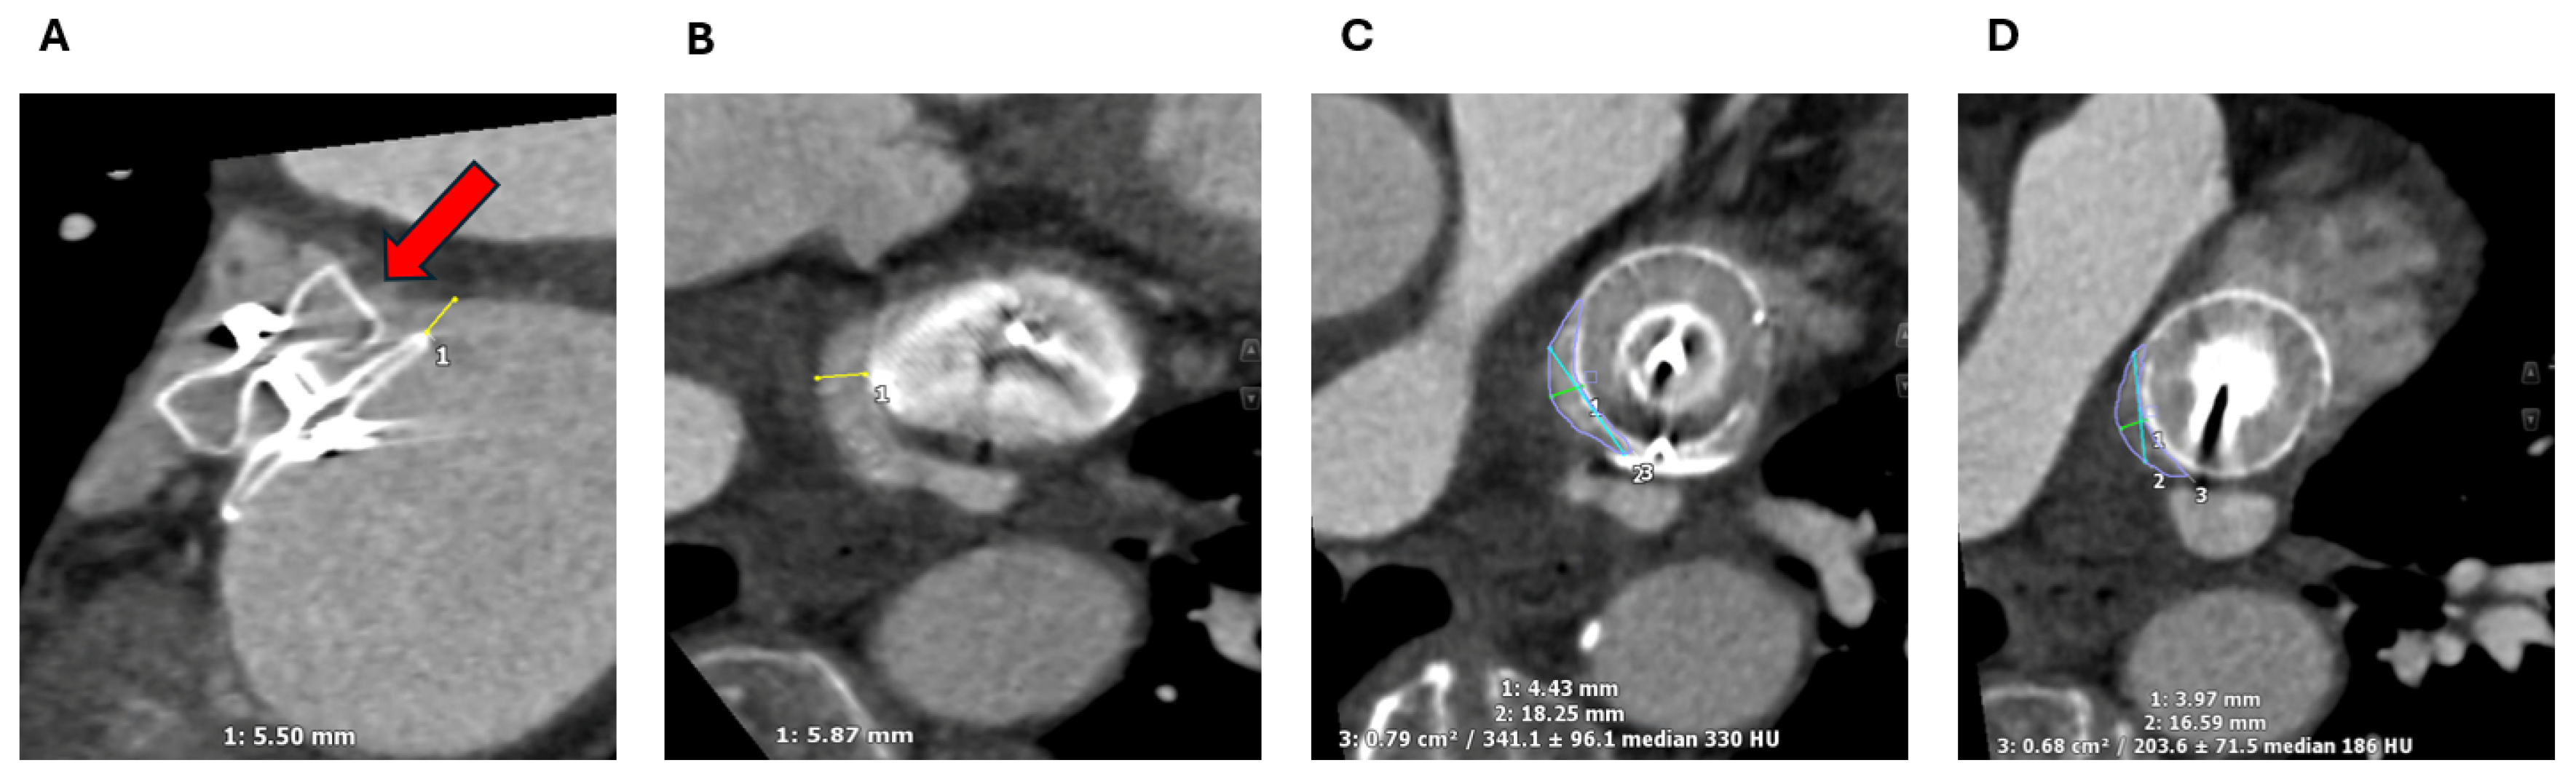

2.1.2. LAA Measurements

2.1.3. Assessment of the Inter-Atrial Septum

2.1.4. Other Anatomical Considerations